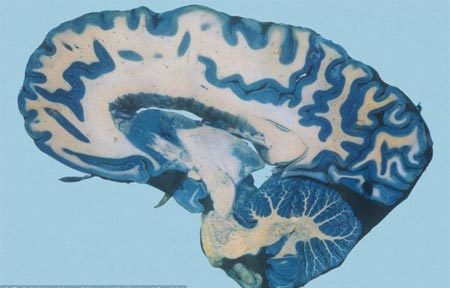

Mặt cắt ngang của một bộ não người điển hình, trong đó chất xám được nhuộm màu xanh. Ảnh: Corbis |

Tiến sĩ Cantor rất ngạc nhiên khi phát hiện các khác biệt rất lớn trong chất trắng ở bộ não của những kẻ ấu dâm so với bộ não của những người bình thường.

Phát biểu trong chương trình "The Agenda", chuyên gia này tiết lộ, bản thân từng hy vọng sẽ khám phá các khác biệt ở chất xám của bộ não, nơi giới nghiên cứu thường phát hiện những biến đổi quan trọng. Lí do là vì, ông quan niệm không có gì trong chất trắng và chúng chỉ đóng vai trò là mô kết nối giữa các phần khác nhau của bộ não.